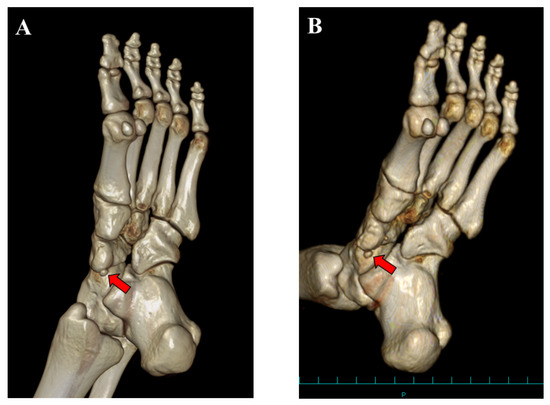

2. Case Presentation